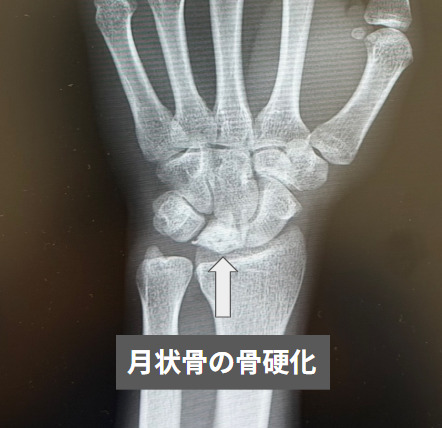

リヒトマン分類のStage 0では、手首に痛みなどの自覚症状があるのみで、単純X線像やMRIでは異常が見つかりません。Stage Iに進行すると、単純X線像では月状骨に異常が見られないか、あるいは線状の骨折が確認されます。MRIのT1強調像では月状骨が低信号を示します。Stage IIでは、単純X線像で月状骨の骨硬化が認められますが、骨の形状は保たれています。Stage IIIになると、月状骨の扁平化や分節化が見られ、これには舟状骨の掌屈回転がないStage IIIA、舟状骨が掌屈回転し手根骨の配列異常を認めるStage IIIB、そして月状骨が冠状面で完全に分断されているStage IIICに分かれます。Stage IVでは、手根骨や橈骨を含む手関節に変形性関節症性変化が見られます。